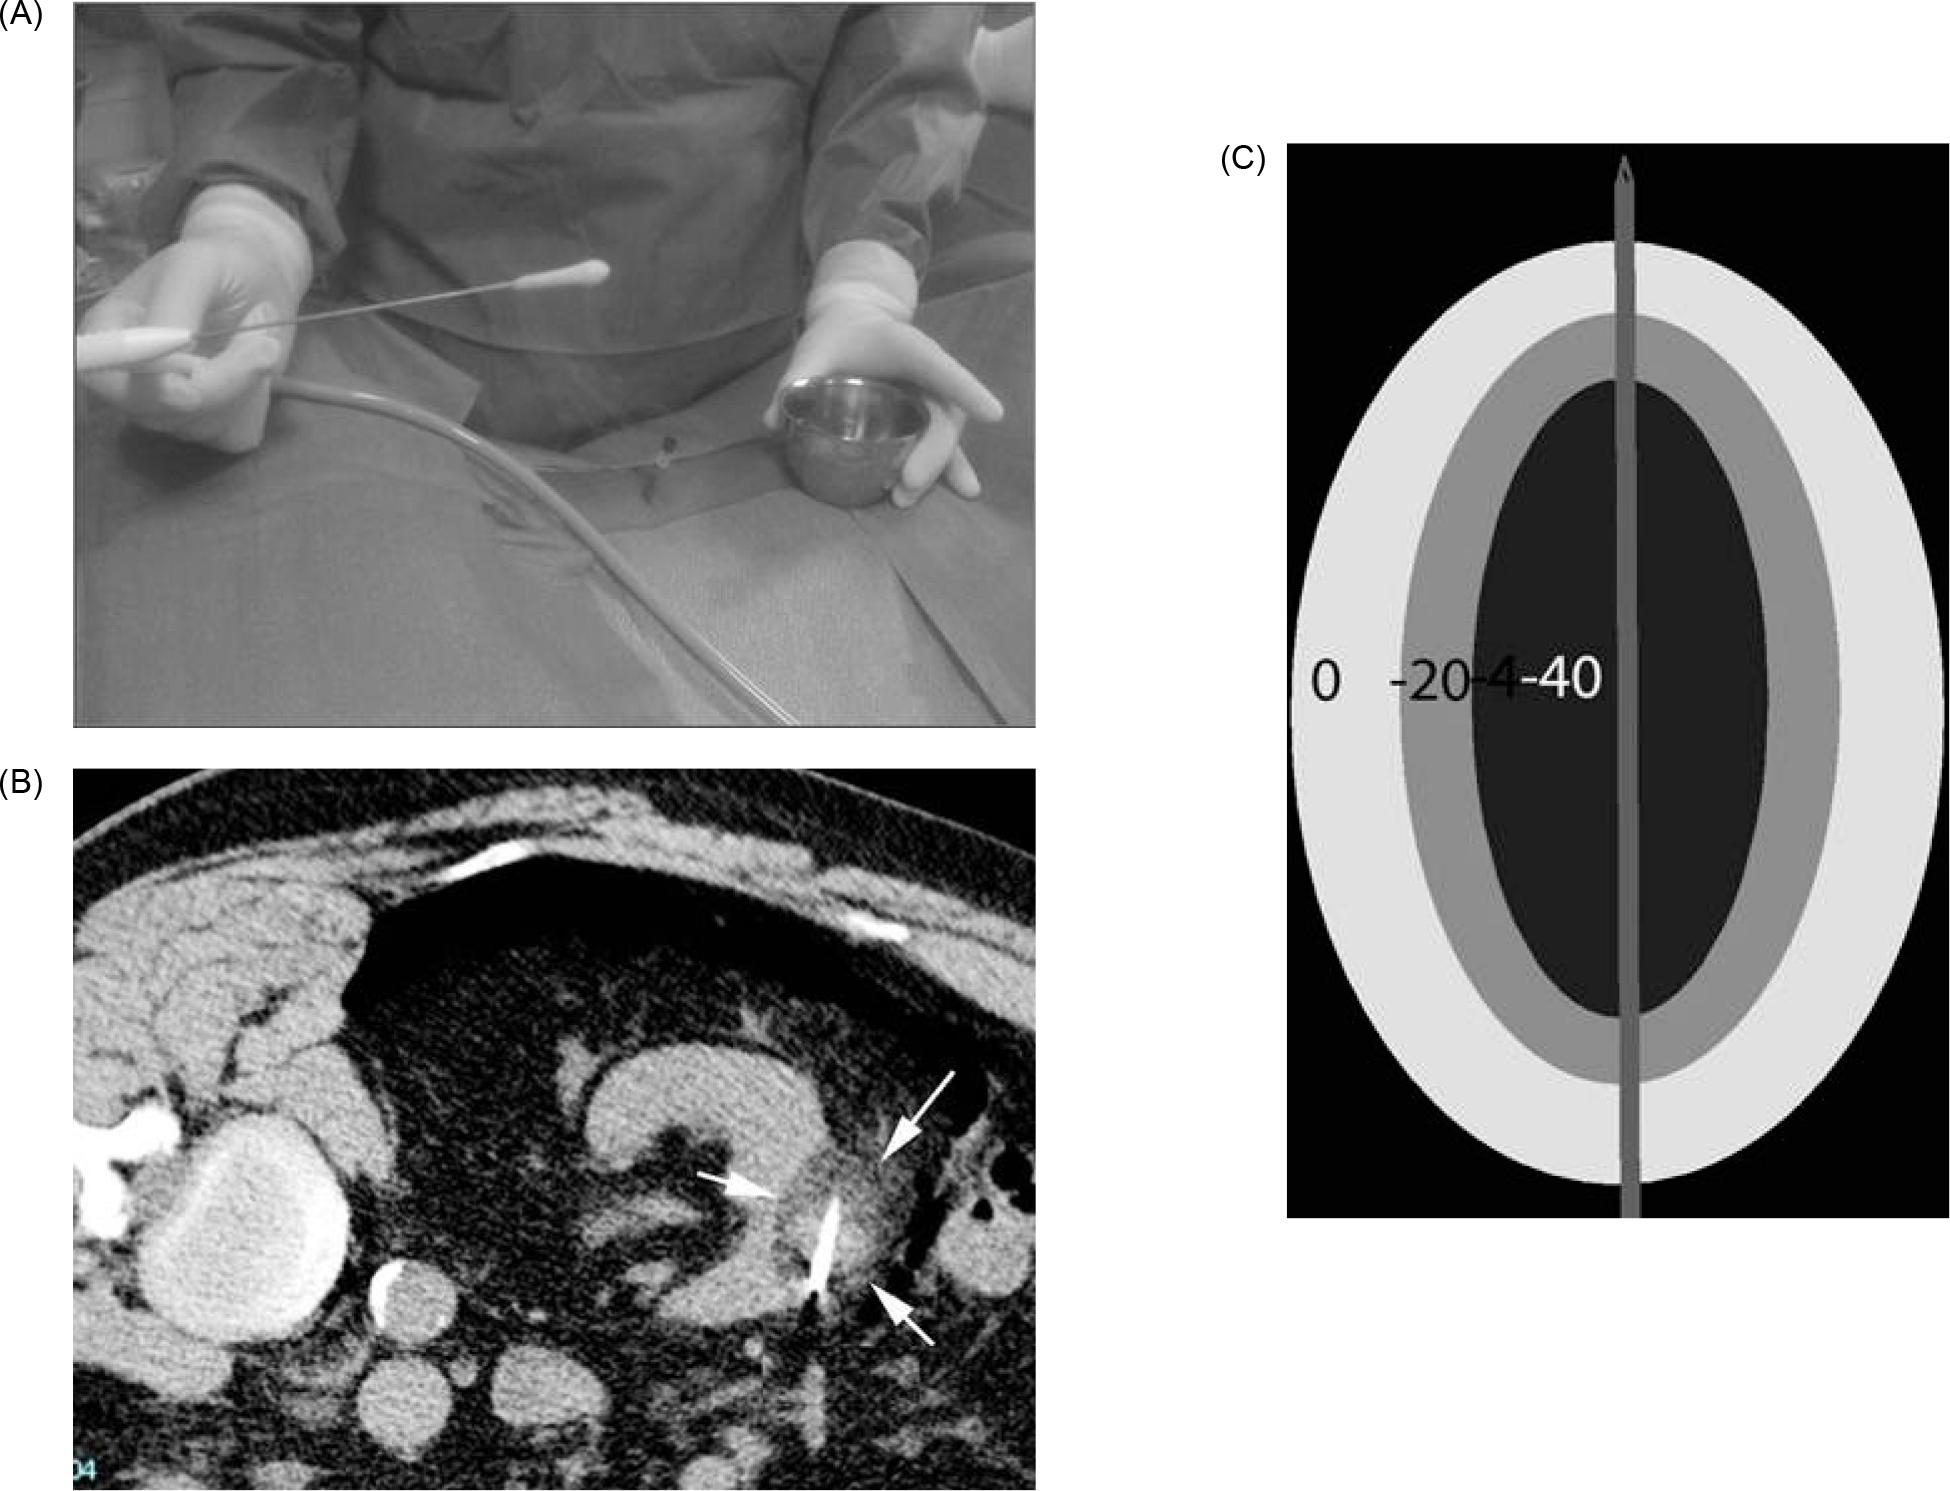

Microwave Ablation

Mechanism

Microwave ablation is a form of electromagnetic radiation that typically oscillates between 900–2500 MHz (36). Like RFA, this fluctuation causes the continued realignment of polar molecules within tissue producing an increase in kinetic energy. This phenomenon, termed “dielectric hysteresis,” translates to rising temperature within the tissue, often above 100°C (15, 36). In MWA, these electromagnetic waves are delivered through one or more antennae inserted into the tissue (27). In contrast to RFA, MWA does not rely on tissue conductivity, and can effectively heat a variety of tissues regardless of electrical conductivity (37). This field effect provides for uniform heat generation (Figure 5). Thus, it is effective compared to RFA for lung, bone, and other tissues with high electrical impedance (37). Further, MWA has an increased ability to overcome the heat sink effect (38). This is an advantage for efficacy within highly vascular organs such as the kidneys, where increased blood flow can lead to the dispersion of thermal energy (27).

Figure 5: Depiction of microwave antenna generating a field of heat.